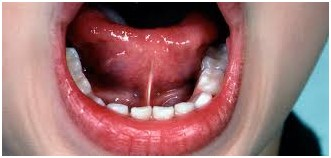

Figura 1 Freio curto

Figura 2 – Freio anterior:

Figura 3 – Freio curto e anterior:

Figura 4 – Anquiloglossia

Quando alterado este pode ser curto, com inserção anterior, ou curto com inserção anterior. Existe ainda o quadro em que a língua se encontra fixa no pavimento bocal chamado anquiloglossia.